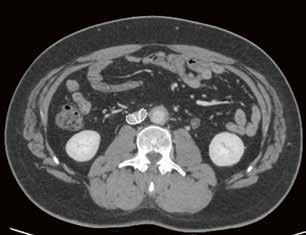

Fall 1:

Biphasische Abdomen-CT bei einer deutlich adipösen Patientin. Hier lässt sich sowohl Dosis sparen als auch die Qualität der Rekonstruktionen verbessern. Beispielsweise findet sich deutlich weniger Bildrauschen, insbesondere im Bereich der parenchymatösen

Portalvenöse Abdomen-CT. Auch hier ist die Dosis am Aquilion Prime SP mit AiCE geringer, zudem auch hier geringeres Bildrauschen mit sehr guter Abgrenzbarkeit, beispielsweise von Leberläsionen.

Abb. 1 a: biphasische Abdomen-CT, Canon Aquilion Prime, Rekonstruktion: AIDR 3D; DLP 1003,6 mGy × cm / 18,1 mSv. Abb. 2 a: biphasische Abdomen-CT, Canon Aquilion Prime, Rekonstruktion: AIDR 3D; DLP 1003,6 mGy × cm / 18,1 mSv. Abb. 1 b: biphasische Abdomen-CT, Canon Aquilion Prime, Rekonstruktion: AiCE; DLP 716,5 mGy × cm / 12,9 mSv. Abb. 2 b: biphasische Abdomen-CT, Canon Aquilion Prime, Rekonstruktion: AiCE; DLP 716,5 mGy × cm / 12,9 mSv. Oberbauchorgane.